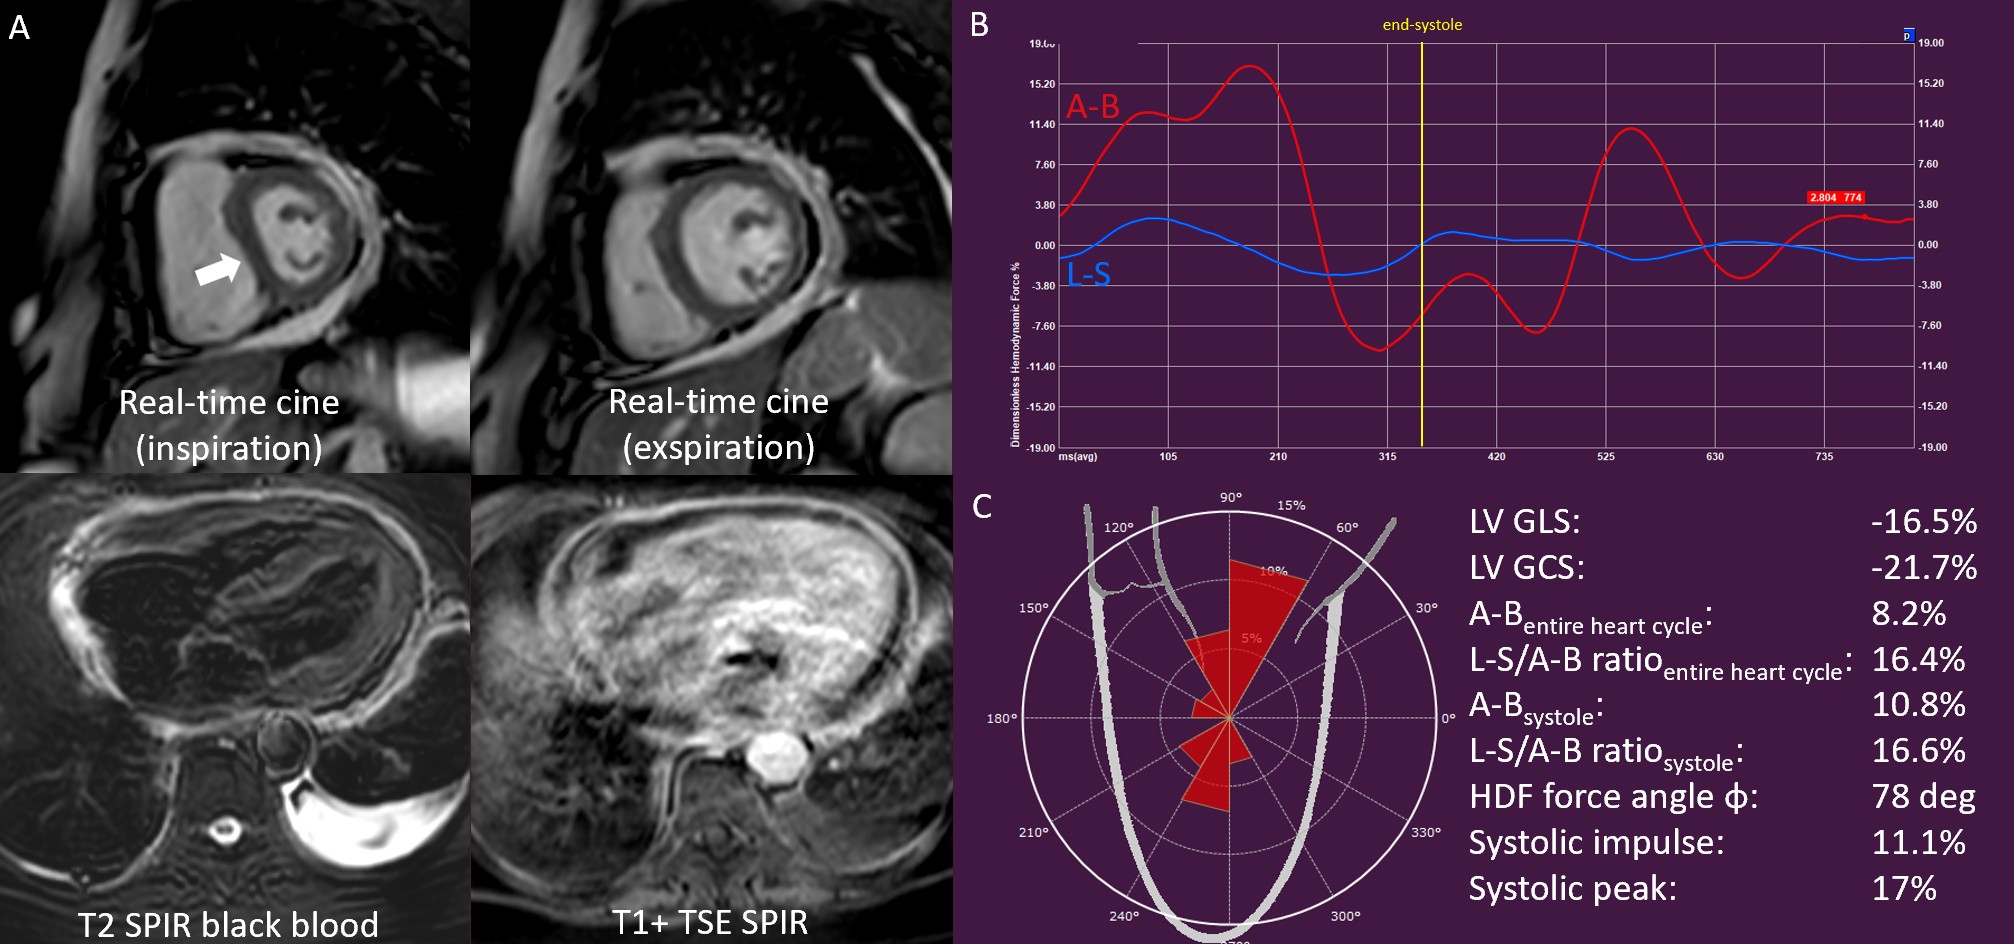

Global longitudinal strain (%) | -22.2±3.9 | -18.11±4.6 | < 0.001 |

Global circumferential strain (%) | -31.9±5.4 | -27.2±6.8 | < 0.001 |

A-B (%) | 21.4 ± 7.3 | 15.3 ± 6.2 | < 0.001 |

L-S (%) | 4.9 ± 2.7 | 4.2 ± 1.5 | 0.145 |

L-S/A-B ratio | 23.1 ± 9.2 | 29.6 ± 10.4 | 0.001 |

HDF force angle φ | 72.4 ± 4.9 | 69.7 ± 5.1 | 0.008 |

Systolic impulse (%) | 23.9 ± 8.3 | 16.4 ± 7.4 | < 0.001 |

Systolic peak (%) | 49.3 ± 19.3 | 33.7 ± 15.0 | < 0.001 |